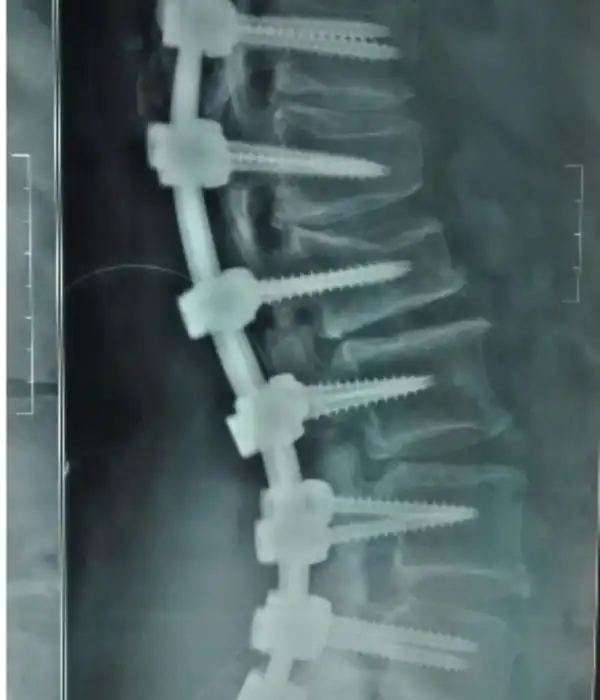

Posterior Instrumental Laminectomy

Degen Scoliosis

Degen Scoliosis Post operative Xray